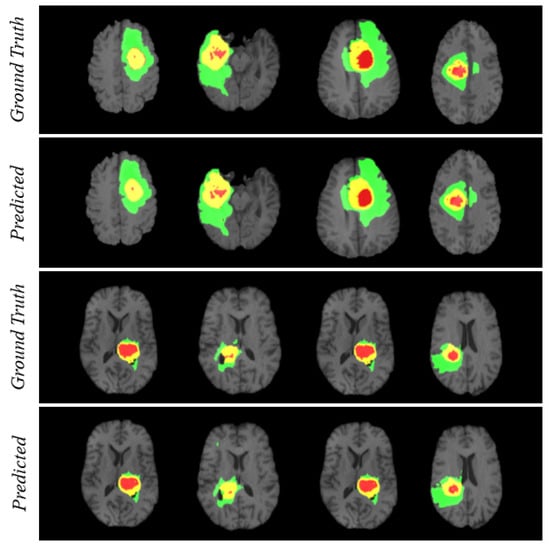

For visualizing the qualitative results, we have added Figure 4. The figure carries eight different cases where the region prediction by BrainSeg-Net is shown along with the labeled ground truth. By comparing both, we can have an idea about the reliability of the segmentation results achieved by BrainSeg-Net. The high resemblance between predicted and ground truth speaks about the high quality of BrainSeg-Net architecture.

Figure 4. Visualization of segmentation performance by BrainSeg-Net architecture. Three colors in each case represents different classes. Red for necrosis and non-enhancing, green for edema, and yellow for enhancing tumor.